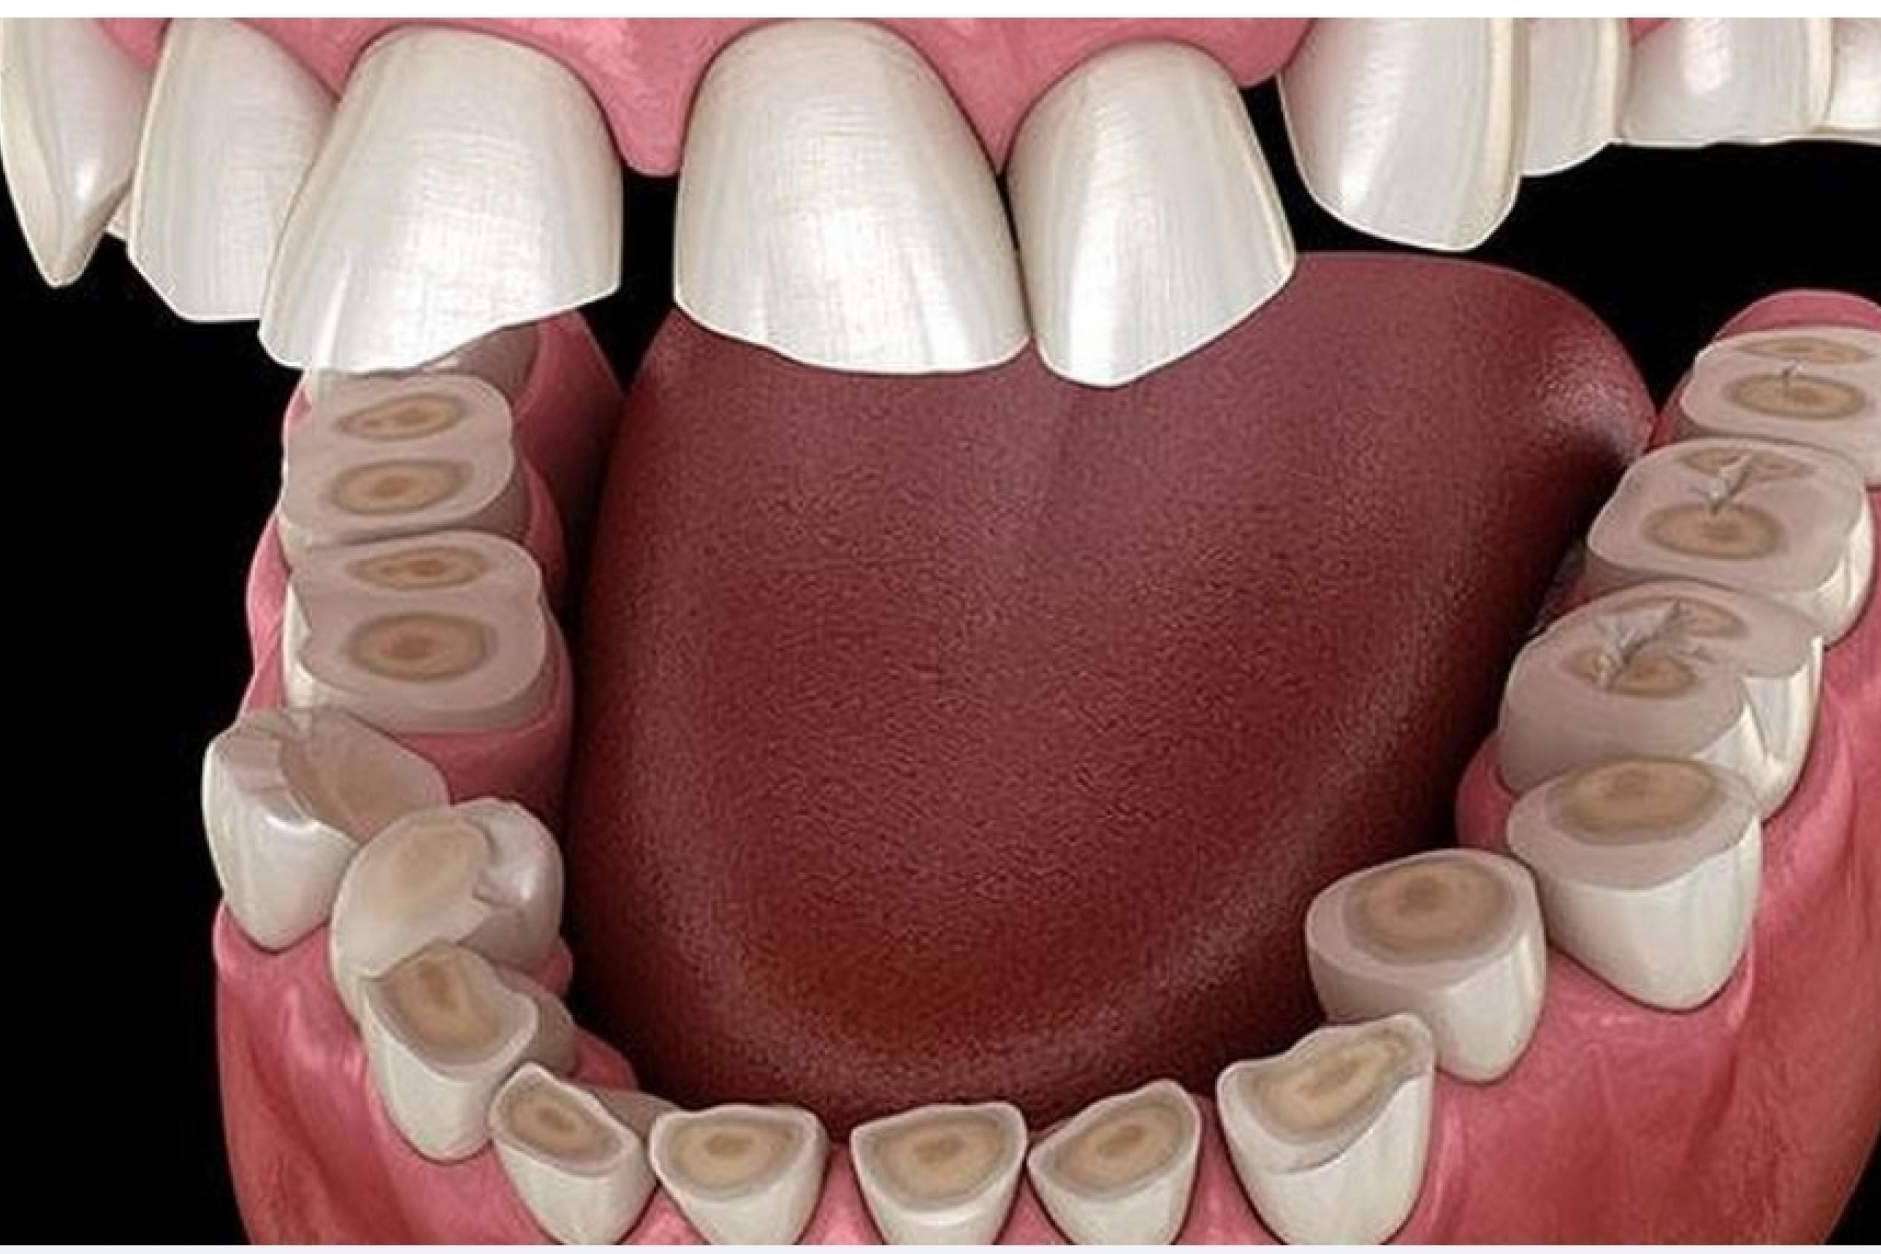

La etapa temprana de la enfermedad de las encías o gingivitis se manifiesta con una significativa inflamación de las encías y sensibilidad. Además, esta se vuelve de color rojo intenso. Asimismo, hay presencia de sangrado durante el cepillado, así como mal aliento.

Si las personas presentan los mencionados síntomas y no acuden al especialista, la gingivitis avanza hasta convertirse en periodontitis, que es una severa infección de las encías que afecta el tejido blando. Es fundamental saber que la enfermedad periodontal en su etapa más agresiva es capaz de destruir el hueso que sostiene los dientes.

En el caso de la existencia de periodontitis, se suministran antibióticos para eliminar la infección bacteriana y se realizan algunos procedimientos dependiendo de cada caso. Algunos pacientes pueden necesitar, por ejemplo, un raspado para quitar el sarro y las bacterias.

Hay casos que requieren métodos quirúrgicos complejos, como injerto óseo o del tejido blando o reposición de piezas dentales, entre otros. Los interesados en ponerse en manos de los profesionales de Dentinova pueden pedir una cita a través de su página web.